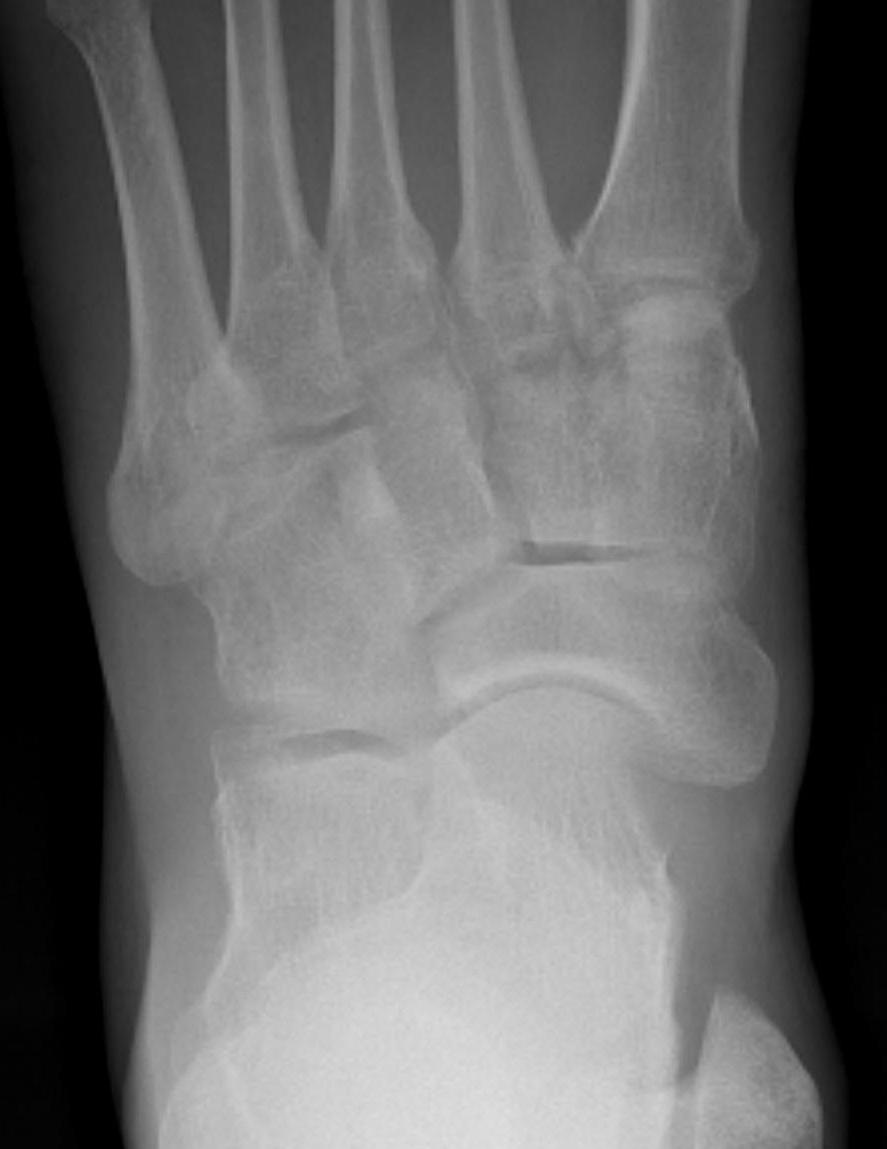

Classification

| Type I | Type II | Type III |

|---|---|---|

|

Small ossicle proximal to insertion In the Tibialis posterior tendon |

Triangular ossicle Connected to navicular via syndesmosis May fracture with injury |

Enlarged medial navicular Cornuate navicular Likely that Type II accessory navicular has fused |

Bone Scan

MRI

Show edema about a symptomatic accessory navicular